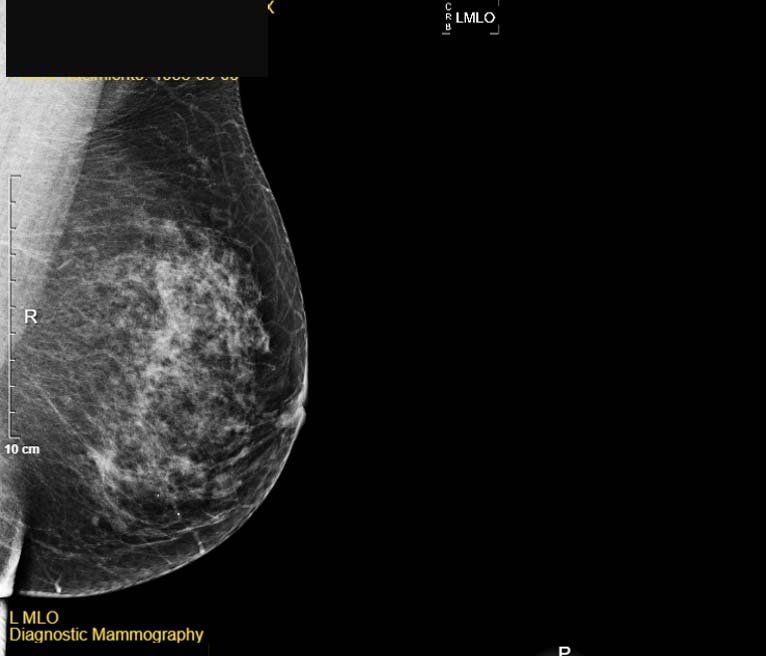

Las mastografías, como vigilancia e imagen diagnóstica, han mejorado con la eliminación de la película radiográfica y el uso rutinario de los detectores digitales. Si el cáncer de mama es detectado en etapas tempranas, hay una probabilidad de cura mayor al 90 %.

Figura 2. La imagen de una mamografía digital es cortesía de Alejandro Rodríguez Camacho.